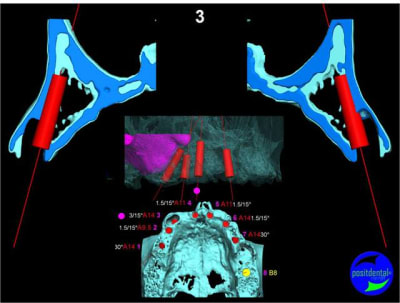

Extraction, pose d’implants Ankylos, pose des piliers Standard définitifs, mise en charge immédiate bi-maxillaire en une chirurgie.

Maxillaire supérieur – extraction 13, 26, 7 implants en MCI, 1 implant en MCR pose summeurs, densification par ostéotme, comblement osseux, bridge provisoire sans fausse gencive avec renfort métallique.

Maxillaire inferieur – extraction 35, 34, 44, 45, 6 implants MCI, comblement osseux, bridge provisoire sans fausse gencive avec renfort métallique.

en attendant la pano voici les coupes de la S.I.A.O.